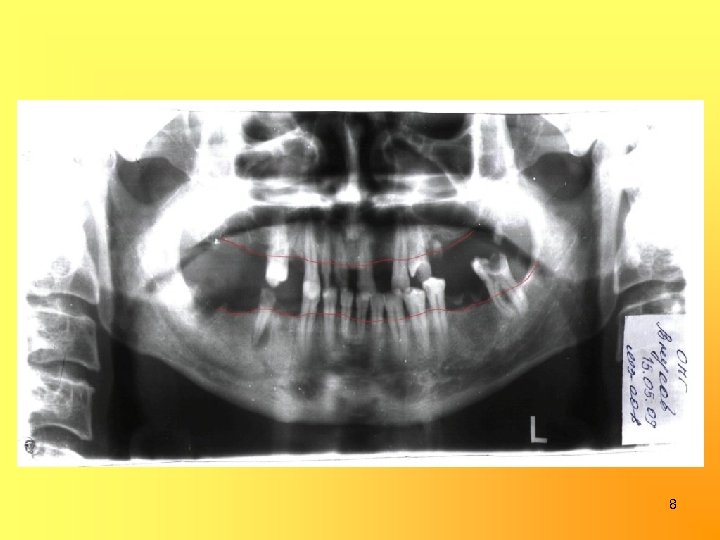

8

Одонтопародонтограмма 0 0, 9 0 1, 1 0, 7 0, 9 0 1, 1 0, 9 0 0 0 ½ 0 ¼¼¼¼ 0 ¼½ 0 0 0 0 8 7 6 5 4 3 2 1 1 2 3 4 5 6 7 8 0 0 0 ¼½½½½¼¼¼ 0 ½ 0 0 1, 3 0 1, 1 0 1, 5 0 0, 5 0, 5 1, 1 1, 3 9

ДИАГНОЗ: Хронический фиброзный периодонтит 16 (ИРОПЗ = 0, 8), 25 (ИРОПЗ = 0, 8), 28 (ИРОПЗ = 0, 7), 36 (ИРОПЗ = 0, 9), 48(ИРОПЗ= 0, 8); Хронический гранулематозный периодонтит 45 (ИРОПЗ=0, 7); Хронический фиброзный пульпит 15 (ИРОПЗ = 0, 5), 13, 12, 11, 23, 24, 37(ИРОПЗ = 0, 6); Средний кариес 34 (ИРОПЗ = 0, 2), 35 (ИРОПЗ = 0, 2); Частичная адентия в/ч и н/ч, 6 класс по Гаврилову (комбинированный); Генерализованный пародонтит средней степени тяжести, подвижность зубов II степени, потеря жевательной эффективности по Оксману = 66%. 11

План лечения: 1. Подготовка к протезированию: • Хирургическое лечение: удалению подлежат – 16, 25, 28, 36, 45, 48 • Терапевтическое лечение: лечение хронического пульпита 15, 13, 12, 11, 23, 24, 37, лечение кариеса 34, 35 • Пародонтологическое лечение: профессиональная чистка, снятие назубных отложений 12

2. Ортопедическое лечение: • Изготовление штампованной металлической коронки 37 • Изготовление культевых штифтовых вкладок на корни 11, 12 • Изготовление металлокерамических мостовидных протезов с опорой 15, 13, 12, 11, 23, 24, 43. • Изготовление бюгельных протезов в/ч и н/ч с замковыми креплениями на 15, 24, 43 и опорно-удерживающими кламмерами на 37 и 35. 13